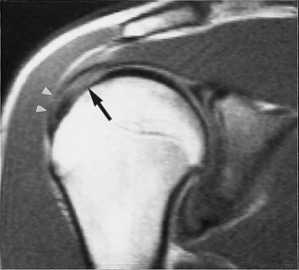

Наиболее типичным (около 85% передних смещений травматической этиологии) является повреждение Банкарта - отрыв фиброзного или фибрознохрящевого фрагмента от края суставной впадины в месте прикрепления связки к суставной впадине с повреждением суставной губы. Кроме того, травма может приводить и к костным повреждениям - перелому гленоидного кольца спереди, костному повреждению Банкарта (то есть повреждению Банкарта в сочетании с переломом) и перелому большой бугристости.

При МРТ плечевого сустава косвенным признаком разрыва вращательной манжеты служит высокий сигнал на Т2-взвешенных от поверхности сустава до субакромиальной (субдельтовидной) сумки. Частичные разрывы чаще всего по передней поверхности сухожилия м.supraspinatus, реже примыкая к большой бугристости или сухожилия м. infraspinatus.